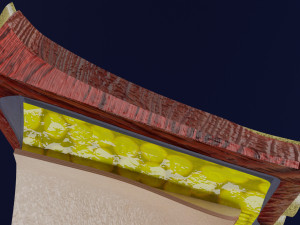

This is a 1:1 scaled model of right breast cut opened in sagittal plane to reveal its internal antomy and histology (schematic). The deeper parts and fascial layers are also depicted to give a very detailed approach to the model. The full layers starting from skin, nipple areola, till intercodtal muscles and ribs are also depicted.